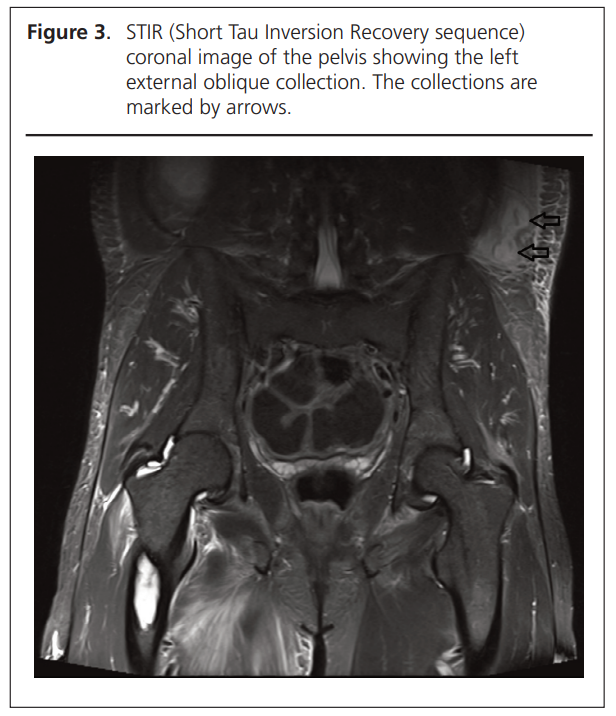

Magnetic resonance imaging (MRI) confirmed multiple large multiloculated intramuscular abscesses with surrounding subcutaneous tissue oedema. The collection involving the right biceps femoris (19.5×6.6×4.1 cm) was associated with marked oedema along the right sciatic nerve. Another infected collection was noted in the left vastus intermedius (12×3.8×3.3 cm) and a smaller 2.4 cm abscess was identified in the left biceps femoris. These are shown in Figures 1, 2 and 3. There was also mild bone marrow oedema at the posterolateral femoral condyle on the left with mild cortical irregularities and left-sided knee joint effusion and synovitis, concerning for early osteoarthritis.

Important and relevant acute investigations were as follows: Hb 142 g/L (NR: 135–180), white blood cells 24.24 (NR: 4.00–11.00), neutrophils 22.1 (NR: 2.0–7.5), C-reactive protein 512 mg/L (NR: <5), estimated glomerular filtration rate >90, serum amylase <20 IU/L. Blood cultures showed no growth. Echocardiogram was normal. Leg ultrasound imaging showed collections in the right biceps femoris muscle (10×7×2 cm), left sartorius muscle (6×4×2 cm) and the left external oblique muscle of the left flank (6×2×2 cm).